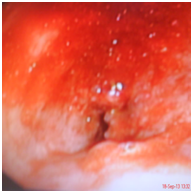

Sixty five year old gentleman is brought to emergency department with acute breathlessness. He had been symptomatic for last three months. He complained of persistent non productive cough followed by some hoarseness and lately breathlessness which was progressive in nature. He had been a current smoker with 25 pack years of smoking. He was hypoxemic on room air and was unable to lie flat. He denied symptoms consistent with COPD prior to his present illness lasting for three months. Routine blood chemistry was unremarkable. Echocardiogram showed normal left and right heart functions. Arterial blood gas revealed pH; 7. 35, PaCO2 of 45mmHg and PaO2 of 60mmHg of on 5LPM oxygen through simple mask. Chest diagram Figure 1 showed normal lung fields with normal hila, tracheal and cardiac contours. Injectable antibiotics, steroid, nebulised bronchodilators were started along with oxygen and non invasive ventilation. After two days of treatment he showed signs of improvement and was comfortable most of the times and tolerated removal of BiPAP for few hours. However, he preferred to maintain sitting posture even when in sleep and resisted lying down on the bed. He was noted to have paroxysmal respiratory distress requiring top-up nebulisation and reinstitution of NIV support and these events continued for next few days. Further imaging was planned in view of this unusual behaviour. Contrast enhanced CT scan of thorax was performed. Right paratracheal tumor was noted with extrinsic compression on trachea (Figure 2A-2C). Malignant growth obstructing trachea as the cause of his symptoms was discussed with the family. Bronchoscopy and stenting with involved risks were explained and informed and written consent was obtained. Videobronchoscopy was performed. Left vocal cord was immobile (Figure 3A). Subglottic trachea was circumferentially encroached by fleshy growth reducing the diameter to almost pin-hole size (Figure 3B & 3C). As bronchoscope was passed beyond the narrowed part the upper and mid tracheal lumen was wide open however encroached on both sides by infiltrating tumor (Figure 3D). Lower third trachea, primary carina and bronchi on both sides were wide and clear (Figure 3E). The dimensions were estimated and 6. 0cm hybrid Nitinol stent was placed in the trachea covering the tumor extension on both ends (Figure 4). Bronchoscope was withdrawn and patient breathed comfortably even in lying down position. Oxygen and BiPAP support were not needed anymore. Nebulization frequency was reduced and also the dose of steroid. Biospy from growth was consistent with moderately differentiated squamous cell carcinoma. He was discharged with advice to follow up with oncology for chemotherapy.

Figure 3a Bronchoscopic view: Left vocal cord palsy.

Figure 3b Bronchscopic view subglottic trachea.

Figure 3c Bronchoscopic view upper trachea.

Figure 3d Bronchoscopic view mid trachea.

Figure 3e Bronchoscopic view beyond carina.